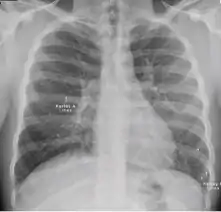

Chest x-ray showing patchy opacification on the upper right and mid-zone lung with fibrotic shadows, as well as bilateral hilar lymphadenopathy.